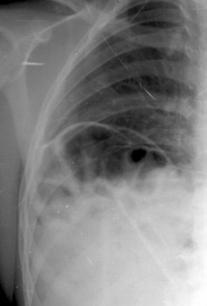

Fig. 13: Pneumonie pneumococica - opacitatiede intensitate medie, omogena cu bronhograma aerica, imprecis delimitata, de forma triunghiulara cu varful la hil.